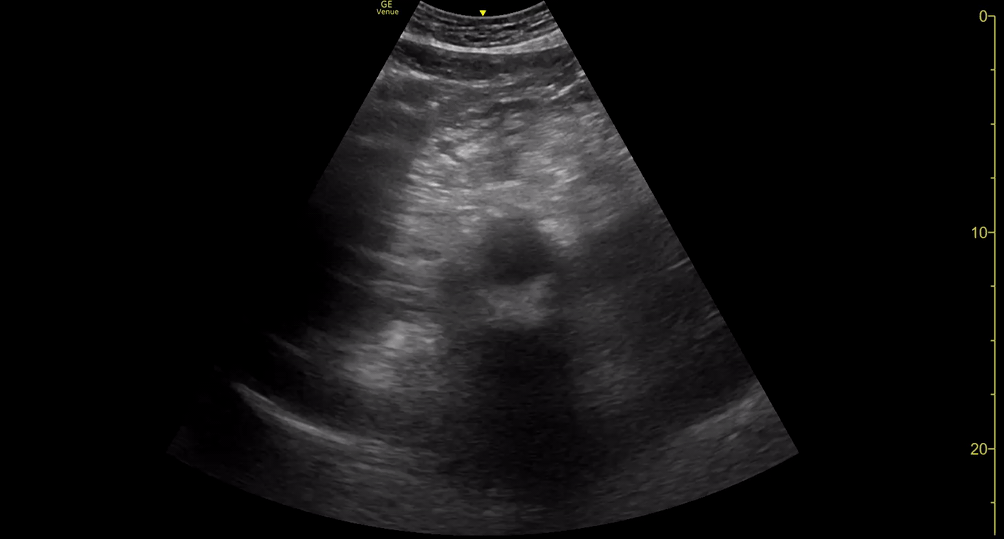

AAA GALLERY

AORTIC ANEURYSM

In adults, the normal anteroposterior aortic diameter is less than 2 cm, and 3 cm or more is considered dilated. The diameter of the common iliac arteries should not be more than 1.5 cm. Most AAAs occur below the renal arteries. As an aneurysm becomes larger it will dilate faster, leading to a greater risk of rupture. This risk remains low if the diameter is less than 5 cm. By contrast, there is a clear tipping point after surpassing 5.5 cm, as the annual incidence of rupture grows from <1% to 9.4% (5)

Once the aorta is identified, measure its diameter from outer to outer wall, as inner wall measurements may underestimate the diameter due to mural thrombus (false negative). While maintaining the transverse orientation, slide the probe distally until the aortic bifurcation and measure the diameter at its middle and distal portions. Then, rotate the probe to the longitudinal position, which is needed to identify saccular aneurysms. Attempt to obtain a view of the aorta that includes the origin of the coeliac trunk or SMA, and measure the AP diameter. Remember, AAA is not ruled out unless the entire length of the abdominal aorta can be visualized and measured.